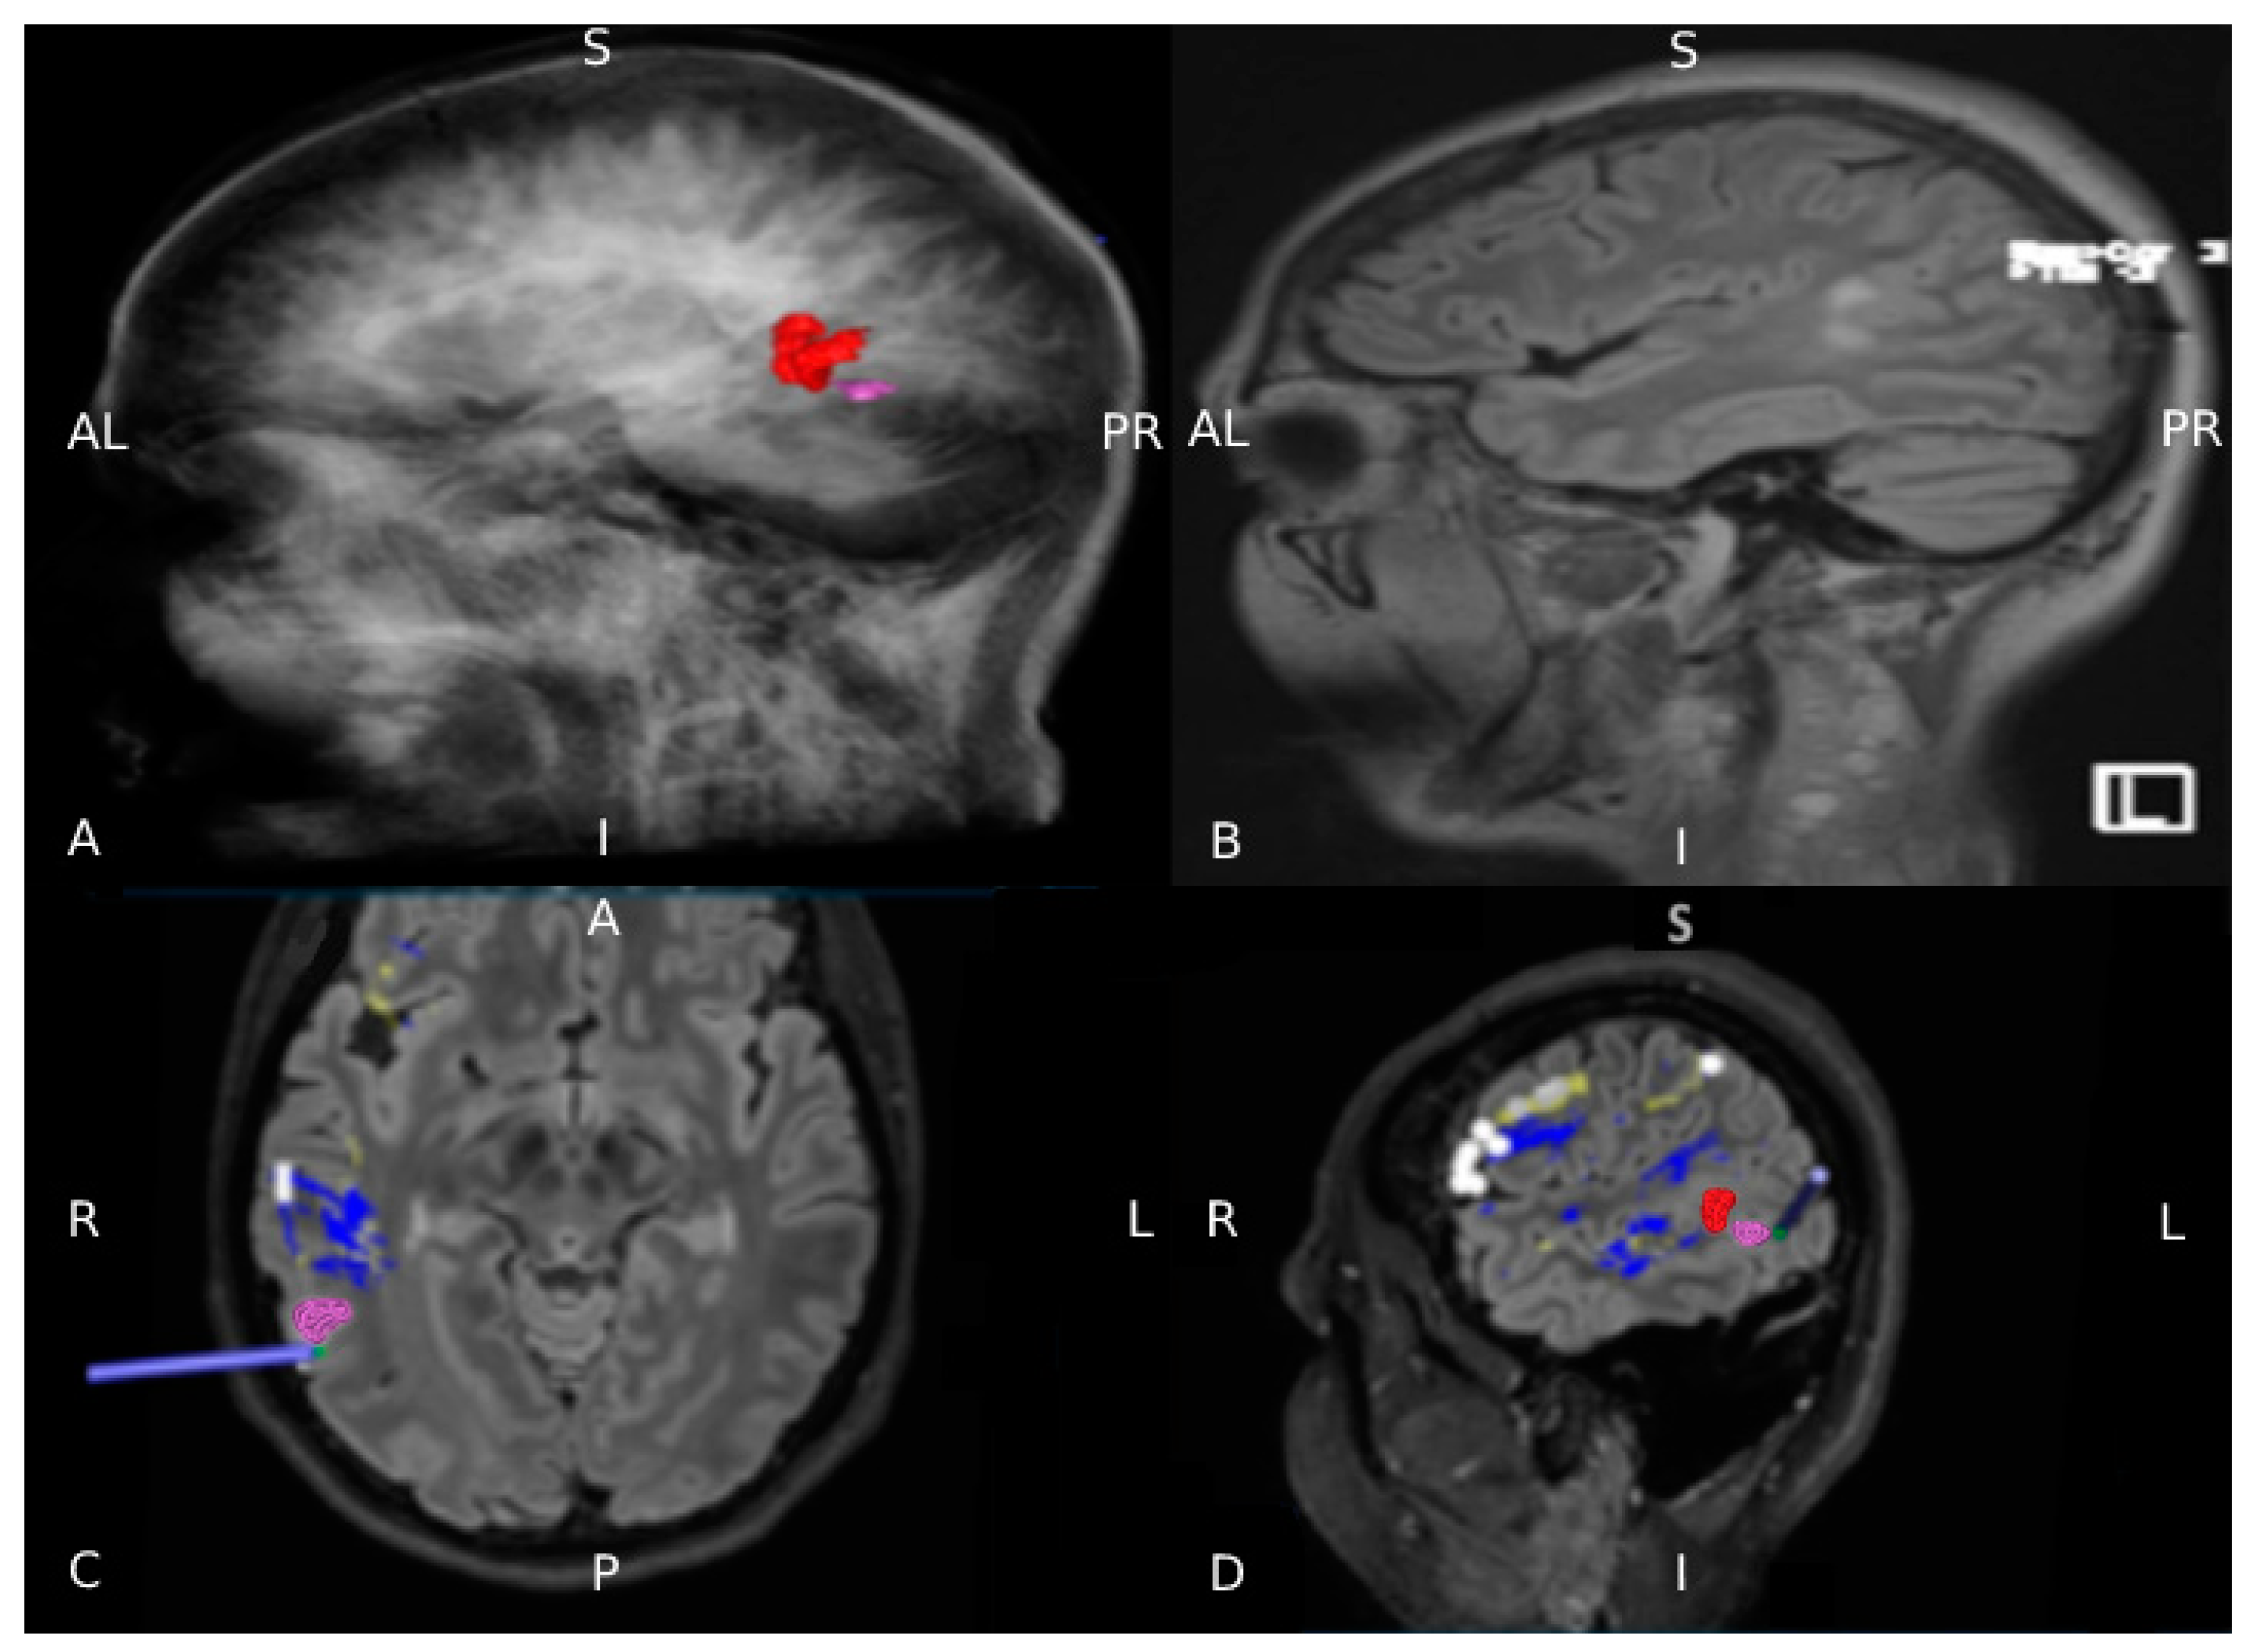

2.5. nTMS Language Cortical Mapping and Off-Line Analysis

2.6. nTMS Based DTI-FT of Language Pathway

2.7. Presurgical Planning